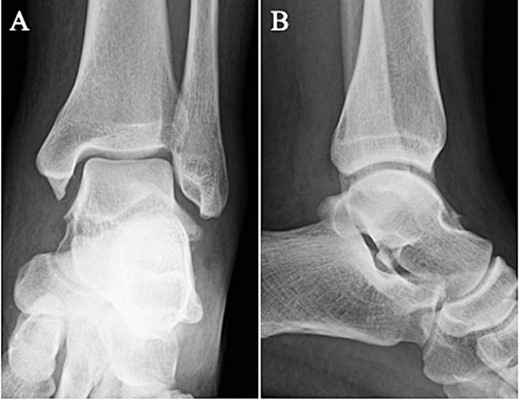

A 24-year-old male basketball player presented to our hospital complaining of left lateral ankle pain during a cutting motion. His height, weight, and body mass index were 172 cm, 64.0 kg, and 21.6 kg/m2, respectively, and he had no history of previous medical conditions. On his first visit to our hospital, he could not walk due to pain. Physical examination revealed swelling, ecchymosis, and tenderness at the lateral aspect of his left ankle. The American Orthopedic Foot and Ankle Society (AOFAS) score was 32 out of 100 points. Plain radiographs of the left ankle showed no abnormal findings in the anteroposterior view, but a fracture line was discovered at the base of the lateral process of the talus in the lateral view (Fig. 1). Non-contrast computed tomography (CT) showed a simple fracture line that extending from the talofibular articular surface down to the posterior talocalcaneal articular surface of the subtalar joint. In addition, the bone fragment was displaced >2 mm (Fig. 2). The patient was diagnosed with Type I LPFT and underwent surgical treatment.

Plain radiographs of the left ankle showed no abnormal findings in the anteroposterior (A) view, but a fracture line was discovered at the base of the lateral process of the talus in the lateral (B) view.